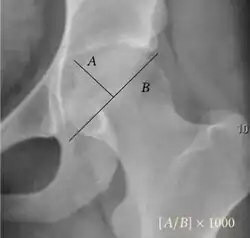

| Acetabular depth ratio |

|

Deepness of acetabulum. | >250